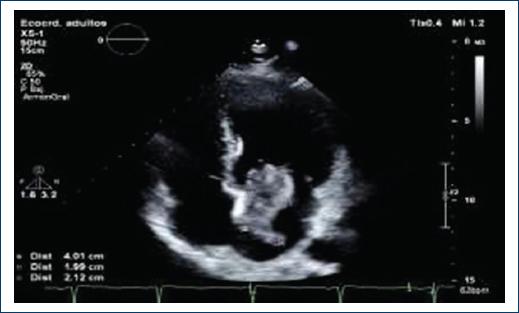

Transthoracic echocardiogram is observed in the left atrium with diameters of 37 × 37 × 49 mm, left atrium volume 38 mL/m2, multilobed and hypomobile tumor with the consistency of different echogenicities and cystic areas, of gelatinous consistency, adhered to the interatrial septum with a base of 25 × 27 mm very proximal at the anterior level of the septum and through it near the aortic valve. The size of the tumor is 40 × 20 mm and the larger lobe is 21 × 20 mm (Fig. 2), slides through the anterior leaflet of the mitral without being attached to it and interferes with the opening, causing functional stenosis of mild degree area by 3D planimetry 2.3 cm2, mean gradient 4 mm Hg, maximum velocity of 1.2 m/s, the insufficiency is mild with a 2 mm contract vein (Fig. 3).

Figure 2 Apical axis four chambers are observed in the left atrium tumor is 40 × 20 mm and the larger lobe is 21 × 20 mm.